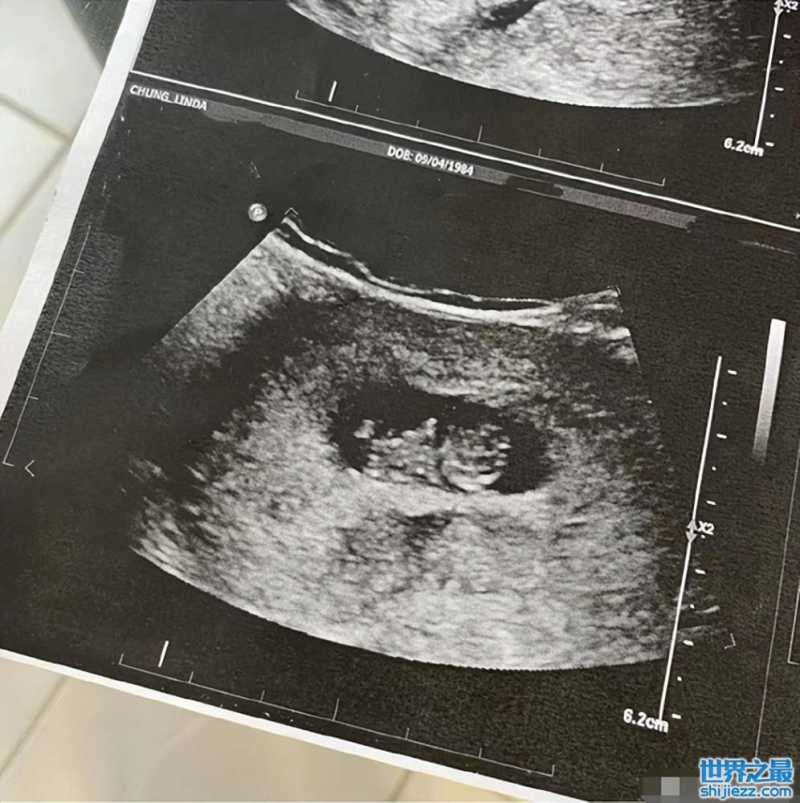

更是直接在社交平台晒出自己的B超照片,从照片中看到虽然宝宝不是很大,但是还是清晰可见的外形。看样子,钟嘉欣一家十分欢喜这个孩子的到来。